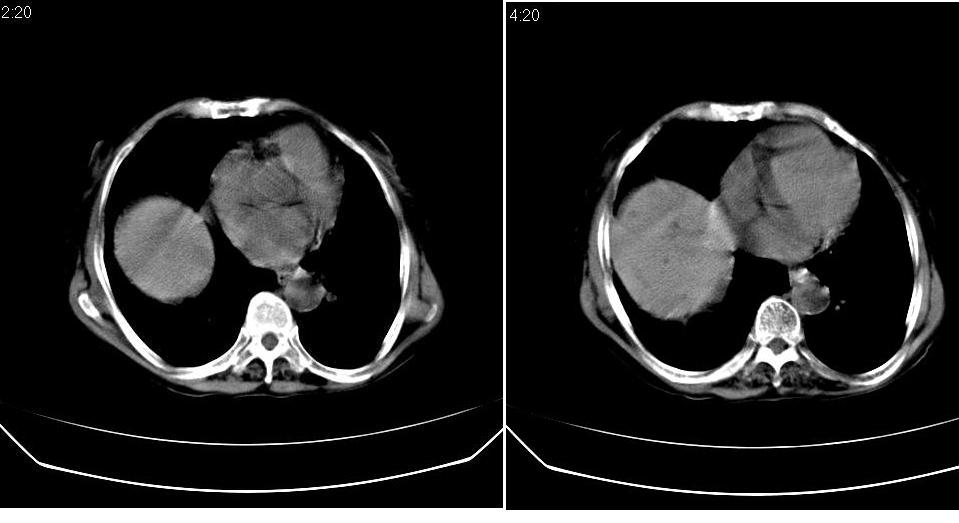

标题: CT23701:上腹部CT平扫

女 76岁,腹痛十余天。

肝癌、肝囊肿。

胆管细胞癌合并感染?建议增强协诊。

考虑肝癌,肝囊肿,建议增强。

肝癌伴肝内胆管扩张,建议增强.

考虑肝癌(胆管细胞型?)并肝内胆管扩张。